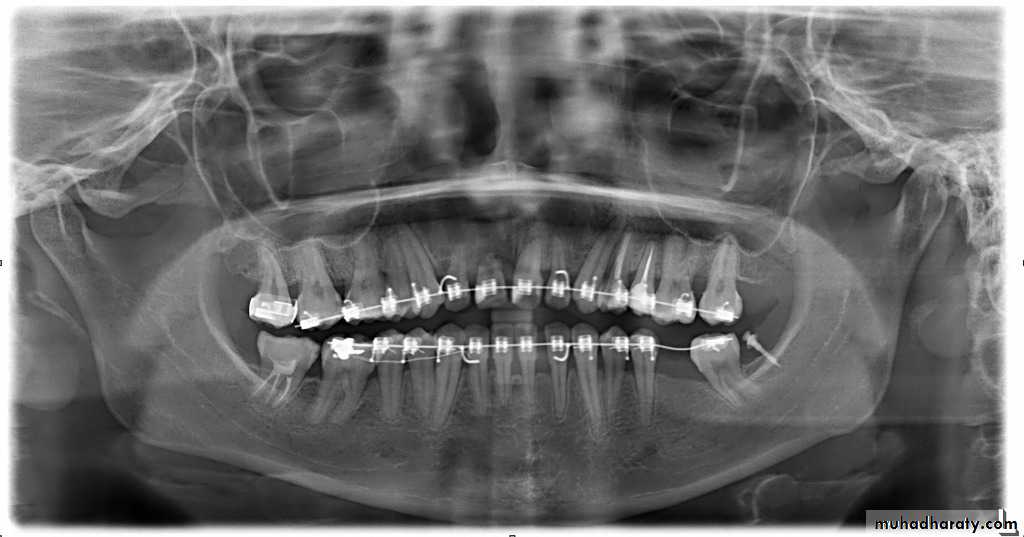

While the use of retainers incorporating posterior bite blocks has been recommended for prolonged retention of anterior open bite malocclusions with unfavorable growth patterns, there is currently a lack of scientific evidence to support this.Patients with a history of periodontal disease or root resorption

In patients with previously treated severe periodontal disease, permanent retention is advised. For those with minimum to moderate disease, a more routine retention protocol can be used. There is evidence of an increased risk of deterioration of lower incisor alignment post-retention in cases with root resorption or crestal bone loss. These cases may therefore benefit from prolonged retention.Growth modification treatment

Fixed retainers are indicated for long-term retention of the labial segments, particularly when there is reduced periodontal support, and for retention of a midline diastema. Fixed retainers are discreet and reduce the demands on patient compliance. However they are associated with failure rates of up to 47%, particularly on upper incisors when there is a deep overbite. In addition, calculus and plaque deposition is greater than with removable retainers. Fixed retainers therefore require long term maintenance.Flexible spiral wire retainers allow differential tooth movement and are particularly useful for patients with loss of periodontal support. Current orthodontic opinion recommends either the use of 0.0215 inch multistrand wire, or 0.030 - 0.032 inch sandblasted round stainless steel wire.